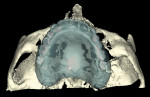

Ten radiopaque markers (gutta percha, Hygenic®, Coltène/Whaledent Group, www.coltene.com) were placed in the maxillary complete denture to prepare the denture for a specific guided- surgery protocol (NobelClinician™ Software, Nobel Biocare USA, LLC, www.nobelbiocare.com).23-30 This protocol uses a dual cone beam computed tomography (CBCT) scan procedure. The first CBCT scan (i-CAT®, Imaging Sciences International Inc., www.imagingsciences.com) was taken with the patient’s dentures in place, and a second CBCT scan was taken of the maxillary complete denture alone. The two scans were exported in Digital Imaging and Communications in Medicine (DICOM) format and loaded into the guided-surgery software, where a 3-dimensional (3-D) virtual working model of the patient was generated (Figure 4 through Figure 7) to enable virtual implant planning to be performed. Because the patient’s denture contained the approved esthetic arrangement of the teeth, the implants could be placed virtually in the most prosthetically favorable position.

The finalized virtual implant plan (Figure 8 through Figure 12) consisted of two 10-mm implants and one 13-mm implant in the maxillary anterior region, which engaged the cortical bone at the inferior border of the nasal cavity. The plan called for two 18-mm implants to be placed in the pterygomaxillary31,32 region at an approximately 45-degree angle to the occlusal plane. These pterygomaxillary implants would provide posterior support for the restoration and eliminate a posterior cantilever.33-36 In order to shorten the span between the three anterior and two posterior implants, three zygoma implants were planned on the pre-surgica lcomputer model to transect through the sinus cavity and engage the zygoma bone. All implants in the virtual planning were external-connection regular-platform implants (Brånemark® System, Nobel Biocare).